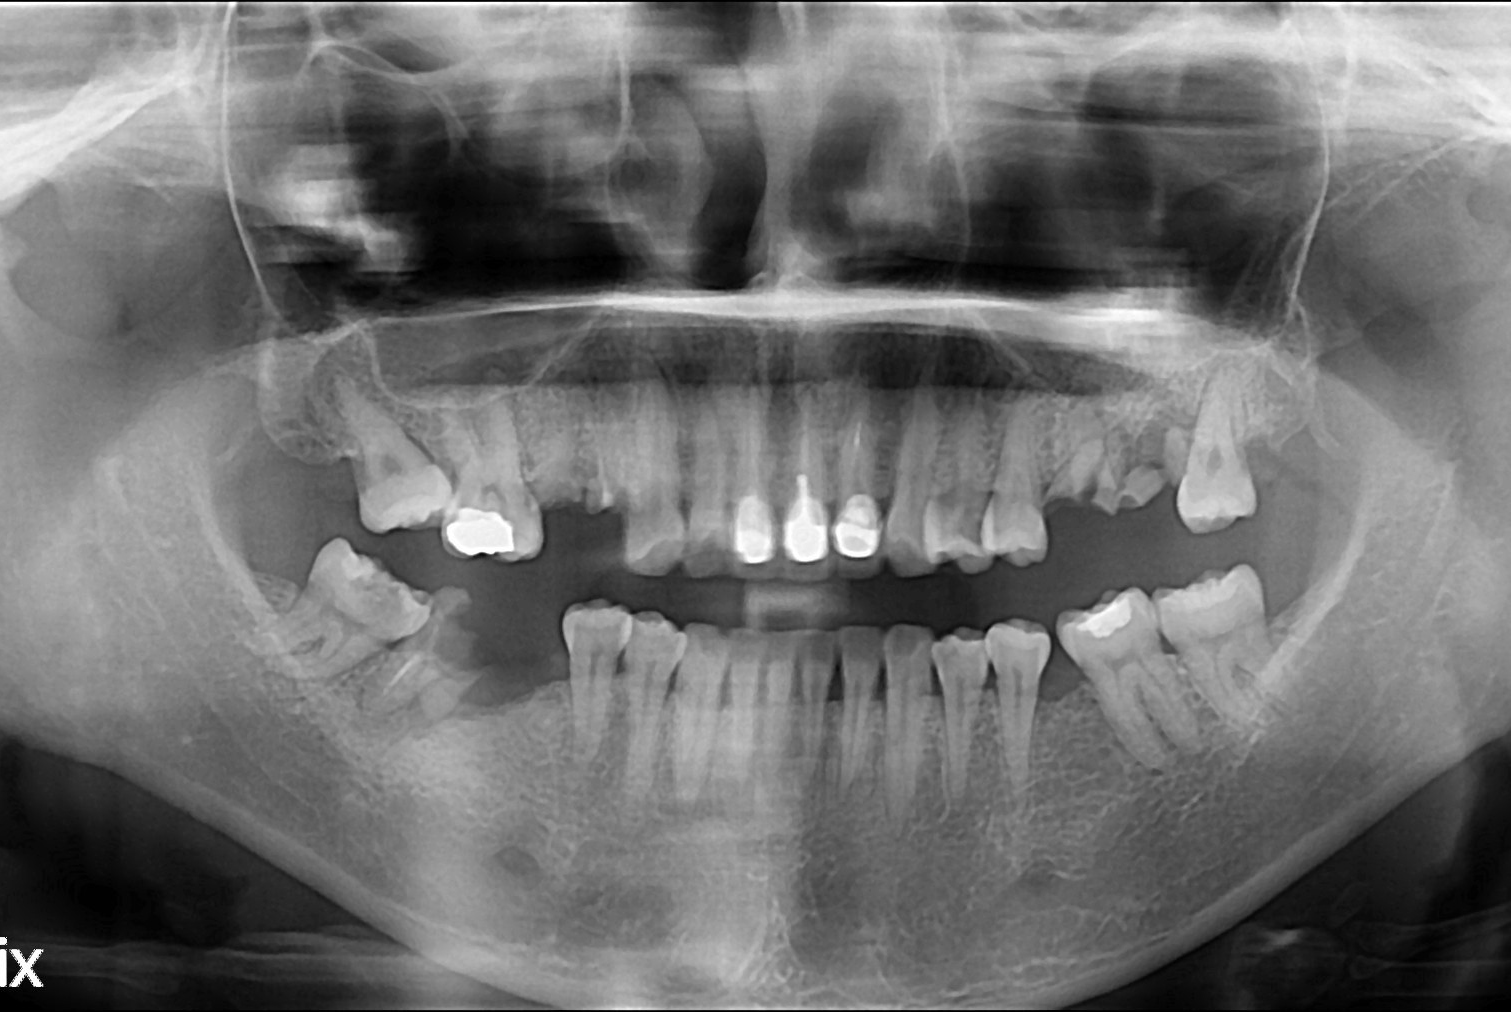

치료전 : 2019-03-18

이춘미 후.jpg